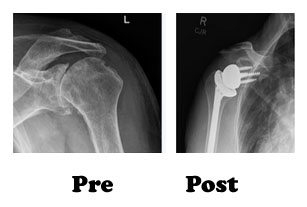

Normal shoulder joint is a ball and socket type of joint, where ball is on the arm bone (humerus) and socket is in the shoulder blade (scapula).

In reverse shoulder, we reverse the normal anatomy of the shoulder so that normal active muscles surrounding the joint will help in its complete range of motion.

Our experience: In 2017 we have started reverse shoulder replacement in a hospital in Amritsar.

The short term results of these patients are very encouraging and persuade us to promote it more for greater benefit of the patients suffering for irreparable losses to the shoulder joint.